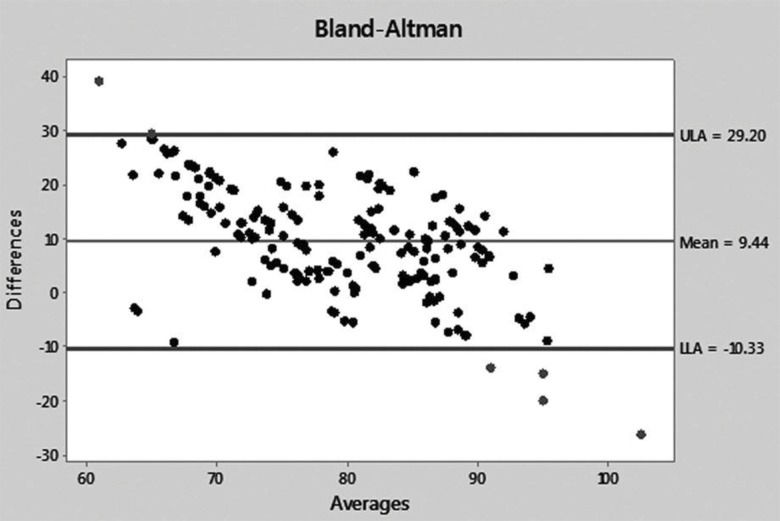

RESULTS:Ultrasound velocity and bone mineral density decreased with demineralization time, and most differences in the pre- and post-demineralization values within each group and between groups were significant: A moderate correlation coefficient (r=0.75956) together with a moderate agreement was determined between both post-demineralization parameters, detected by the Bland-Altman method.

The correlation between UV and BMD progressively increased with the post-demineralization period (G6: r=0.38308, p=0.0002; G12: r=0.64451, p<0.0001; G24: r=0.88733, p<0.0001; G36: r=0.89270, p<0.0001), with a relatively high overall correlation of r=0.75956 (p<0.0001) (Figure 7).

UV and BMD figures were then transformed into percent values of baseline, taking the pre-demineralization values as the baseline. The differences and averages of the obtained values were then applied to a Bland-Altman graph to evaluate the agreement between the two methods. The Bland-Altman graph allows for visualization of how much each difference deviates from zero (bias), the dispersion of the differences around the average (error) and the tendency of the distribution. A perfect agreement occurs when the mean (bias) is zero and the dispersion between the upper (ULA) and lower (LLA) limits of agreement is very small or as close as possible to the mean line; data above ULA and below LLA are not in agreement. In the present case, a moderate agreement was observed because the mean was well above the zero line [9.44] and the average dots were dispersed around the mean line, although concentrated between the ULA and LLA lines. A single case was above ULA, while four cases were below LLA (Figure 8). The dot distribution also showed that lower percent differences between UV and BMD corresponded to averages closer to 100 and that this tendency of the comparison likely indicates that the agreement between the two methods is easier to detect in normal untouched bones.

The demineralization intervals (6, 12, 24 and 36) selected in our experimental design were short because we intended to check the UV capability to detect small differences between intervals. The degree of demineralization was verified by DEXA examination at all time points (6, 12, 24 and 36 hours) of the investigation to ensure that the demineralization method was as effective as we believed and that the results of the UV and BMD measurements obtained could be compared among groups without restriction. Accordingly, the mean post-demineralization UV and BMD values progressively and significantly decreased in a linear manner with demineralization time. UV reached approximately 74% of the average pre-demineralization value and 82% of the 6-hour post-demineralization (G6) value at the 36-hour demineralization (G36) time point; BMD followed that behavior, reaching 65% and 81.5%, respectively, for the same comparisons. The intra- and inter-group differences were significant for most comparisons for both separate UV and BMD data and also between UV and BMD, indicating a moderately positive (r=0.75956) correlation coefficient and a favorable agreement between the two methods according to the Bland-Altman graph. These findings indicate that the methods are highly similar and that either method can be used to assess the loss of mineral content in cortical bone.